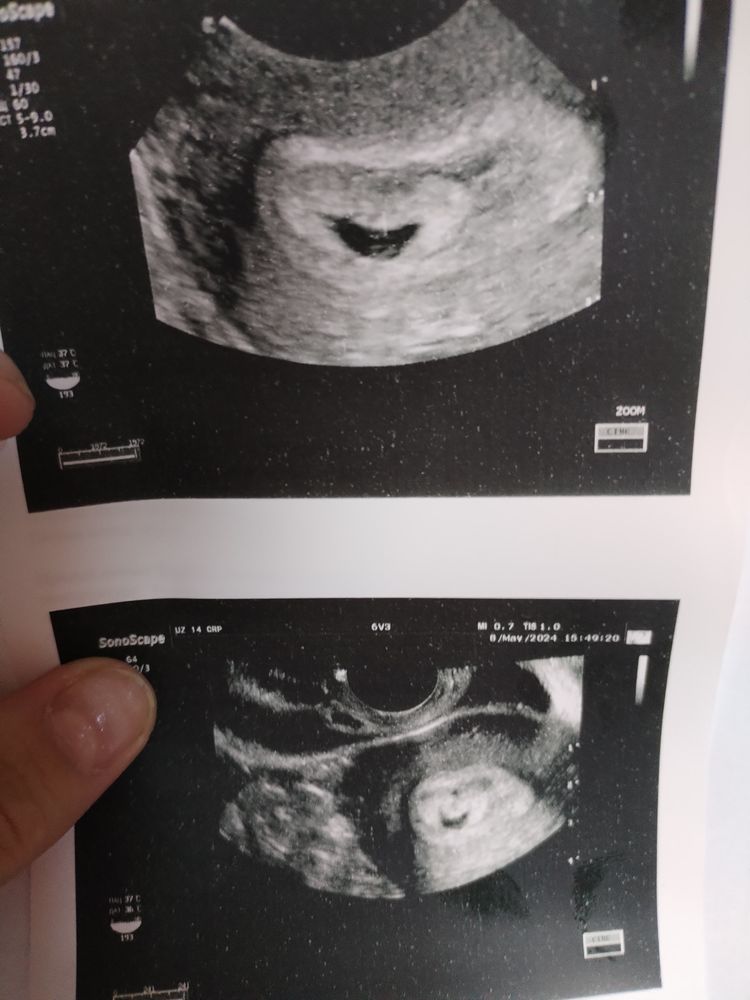

На сроке 5.3 ПЯ было в матке 3.8, на 7.0 пя 12мм, сегодня 7.5 - 13.4мм. есть желточный мешочек, но эмбриона нет. ПЯ деформировано. Узист отправляет на чистку, а врач в больнице сказал ещё ждать. ХГЧ был вчера 20.5 тыс. Врач сказал повторить через 48 часов ХГЧ и если он растет - ждать. Типо такое бывает. Я на Дюфастоне, фраксипарине, папаверин на ночь. Может кто то с таким сталкивался? Я понимаю и сама врачу говорила о том,что знаю нормы прироста. Он сказал,что все понимает, но почистить всегда успеет. Сказал повторить УЗИ 17 числа.

Не появится уже ничего,у меня с плохим ростом пя эмбрион появился в маленьком пя,но была замершая

В 5 недель пя 3 мм

В 6 недель пя 7 мм,ктр 3 сб+

В 7 недель пя 12,ктр 8 сб +

В 7,5 нелель пя 15,ктр 15 сб - замершая,в моем случае пя плохо росло и задавило эмбрион,а в вашем эмбрион замер на очень маленьком сроке и его не видно по узи и пя ещё плохо растет

Анэмбриония это,у вас пя плохо выросло и до 25 мм оно не дорастет,по нормам пя по 1 мм в сутки растет,а у вас за 5 дней выросло на 1,4 мм,оно перестало уже расти,у вас в 5 недель пя 3,8 мм было,за 2,5 недели при нормальной беременности пя уже выросло бы больше 20 мм и был бы эмбрион и сб,хгч неинформативен,при анэмбрионии он может расти